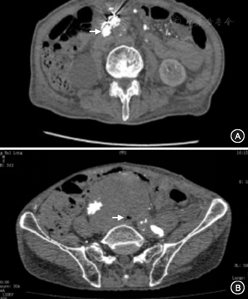

入院时8例患者血液白细胞计数增加,2例血液白细胞计数始终在正常范围。3例血液细菌培养阳性,其余病例多次培养均为阴性结果。增强CT检查发现9例患者腹主动脉瘤周围呈现明显的炎症征象,其中6例瘤囊内出现气泡影(图1),伴有Ⅰ型和Ⅱ型内漏各1例;1例患者多次增强CT检查未显示异常。2例行腹主动脉瘤腔穿刺,其中1例吸出黏稠黄色脓液,另1例抽吸液细菌培养阳性。3例患者接受小肠镜检查,确诊1例AEF。

2例患者未发现明显诱因,其余8例患者存在可能的感染源。其中4例发现AEF(1例为小肠镜检查确诊)(图2);3例EVAR术前即有发热表现,并且增强CT显示瘤体不规则、瘤壁增厚、瘤体周围呈现明显炎性反应等炎性腹主动脉瘤特征,再次手术过程中也给予了证实(图3);1例此次发病前有明确的上呼吸道感染及败血症病史。

1例患者放弃二次手术,1例因耐受力较差故仅行清创引流术,7例行腋动脉——双侧股动脉人工血管旁路+支架切除+清创术,1例行双侧腋动脉——股动脉人工血管旁路+支架切除+清创术,手术均为Ⅰ期完成并获得成功。手术步骤为先建立解剖外人工血管旁路,然后经腹部正中切口显露腹主动脉,于肾动脉开口上方或膈下水平临时阻断腹主动脉,纵行切开瘤体前壁并取出支架,二次手术中移除支架后发现腹主动脉瘤右侧壁溃疡(图2A),清理后显示空肠中段2 cm直径瘘口(图2B),随后将阻断钳移至肾动脉水平以下,并以3-0及4-0尼龙线双重连续缝合腹主动脉残端以及髂动脉残端。尽量清除瘤壁组织及瘤腔内容物,缝扎腰动脉开口。由于可用材料有限,本组病例均采用解剖外人工血管旁路来重建下肢血运(图4)。创面以0.5%碘伏溶液反复浸泡3次,每次10 min,随后以大量生理盐水冲洗创面并留置思华龙引流管。